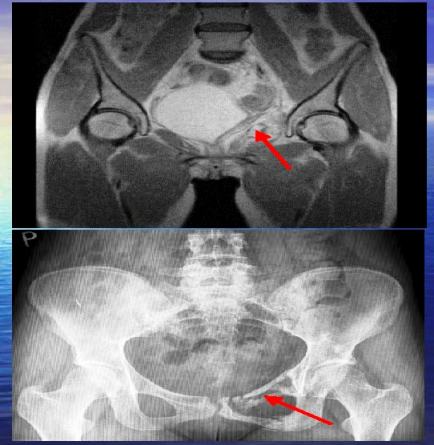

- realizována pouze biopsie tumoru - Histologie:- sex cord stromaltumor, vs tumor z buněk granulosy-možný původ z ektopickeho ovaria (pozn-ektopické ovarium se peroperačě nenašlo) –metastatické postižení os pubis vlevo

- Postoper.CHT:4x BEP ––parciparciáí regrese nálezu v MP přetrvává pozitivita os pubis

- Hodnocení stavu: parciální odpověď trvá metastatická nemoc odeslána na paliativní RT

Obr.1

- PNET/ Ewingův sarkom, origo v os pubis